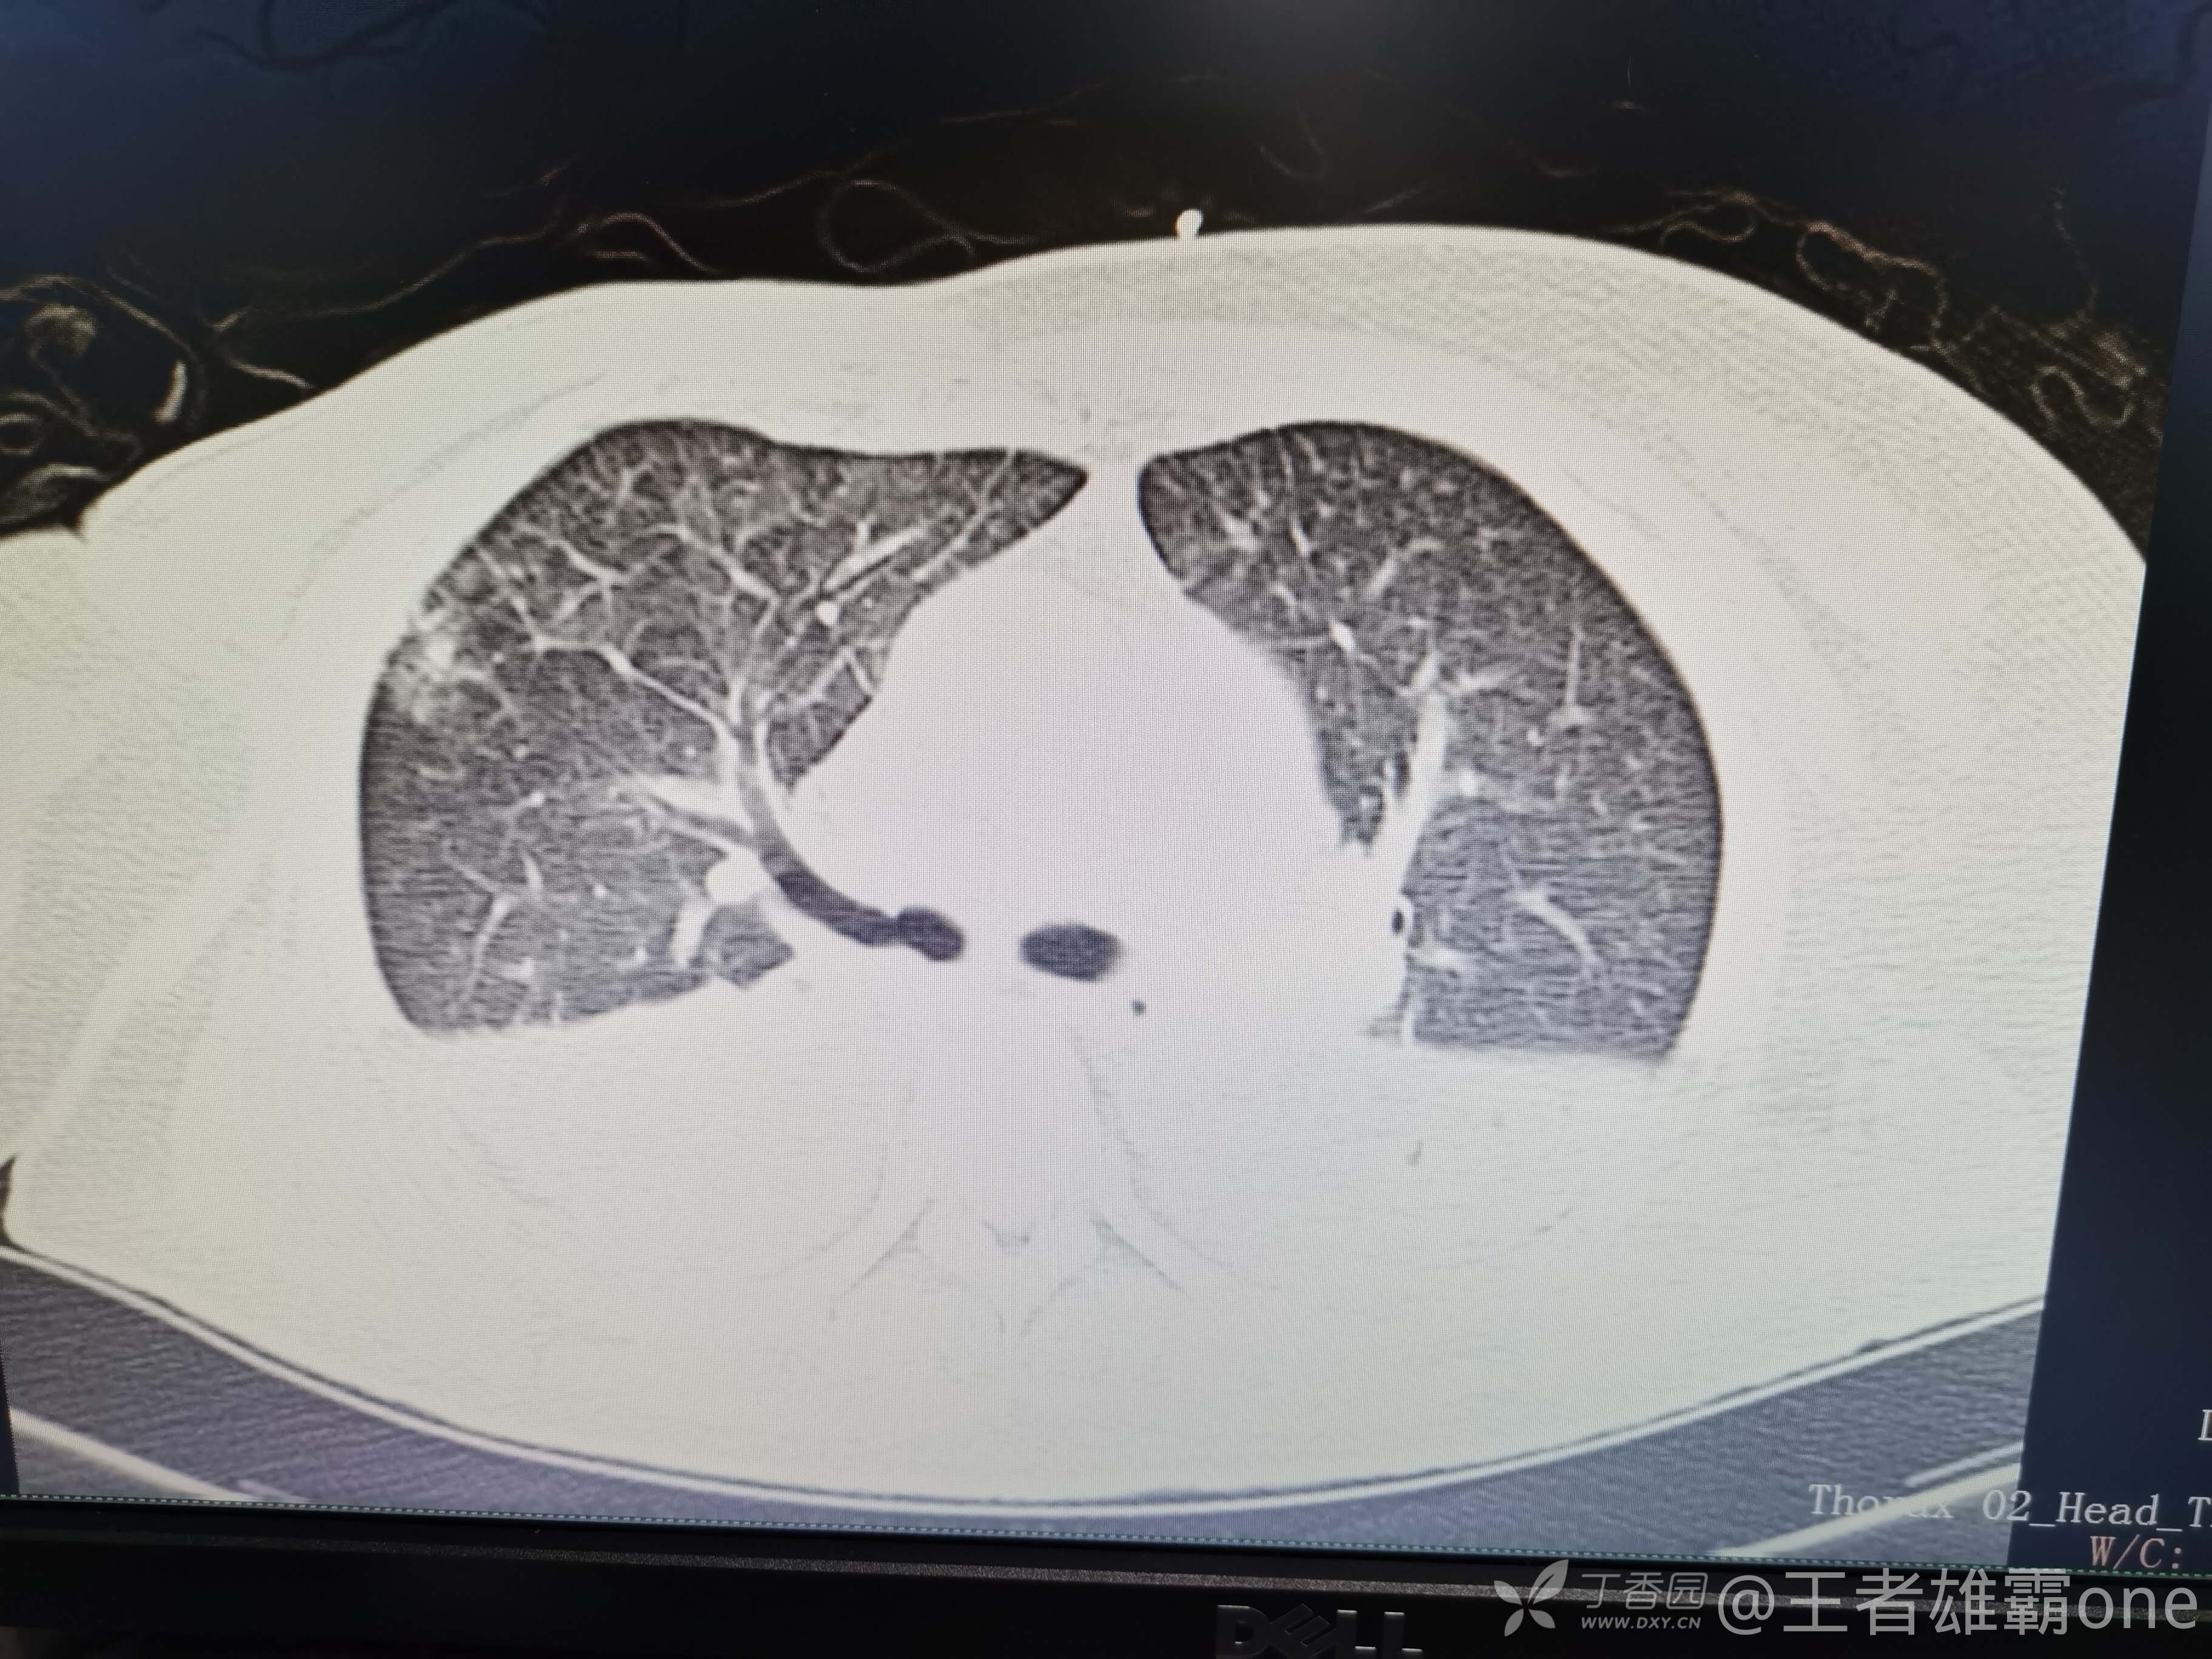

西门开心 推荐63岁女性,因车祸致短暂神志不清、多处疼痛4h入院。简单病史:伤后送至医院急诊就诊。完善头胸腹CT等检查,完善新冠核酸、血常规等化验。血常规提示血红蛋白62g/L。头颅CT提示未见明显外伤性改变。胸腹部CT视频见下:

5.肺挫伤

6.双侧多发肋骨骨折

12.双侧胸腔少量积液